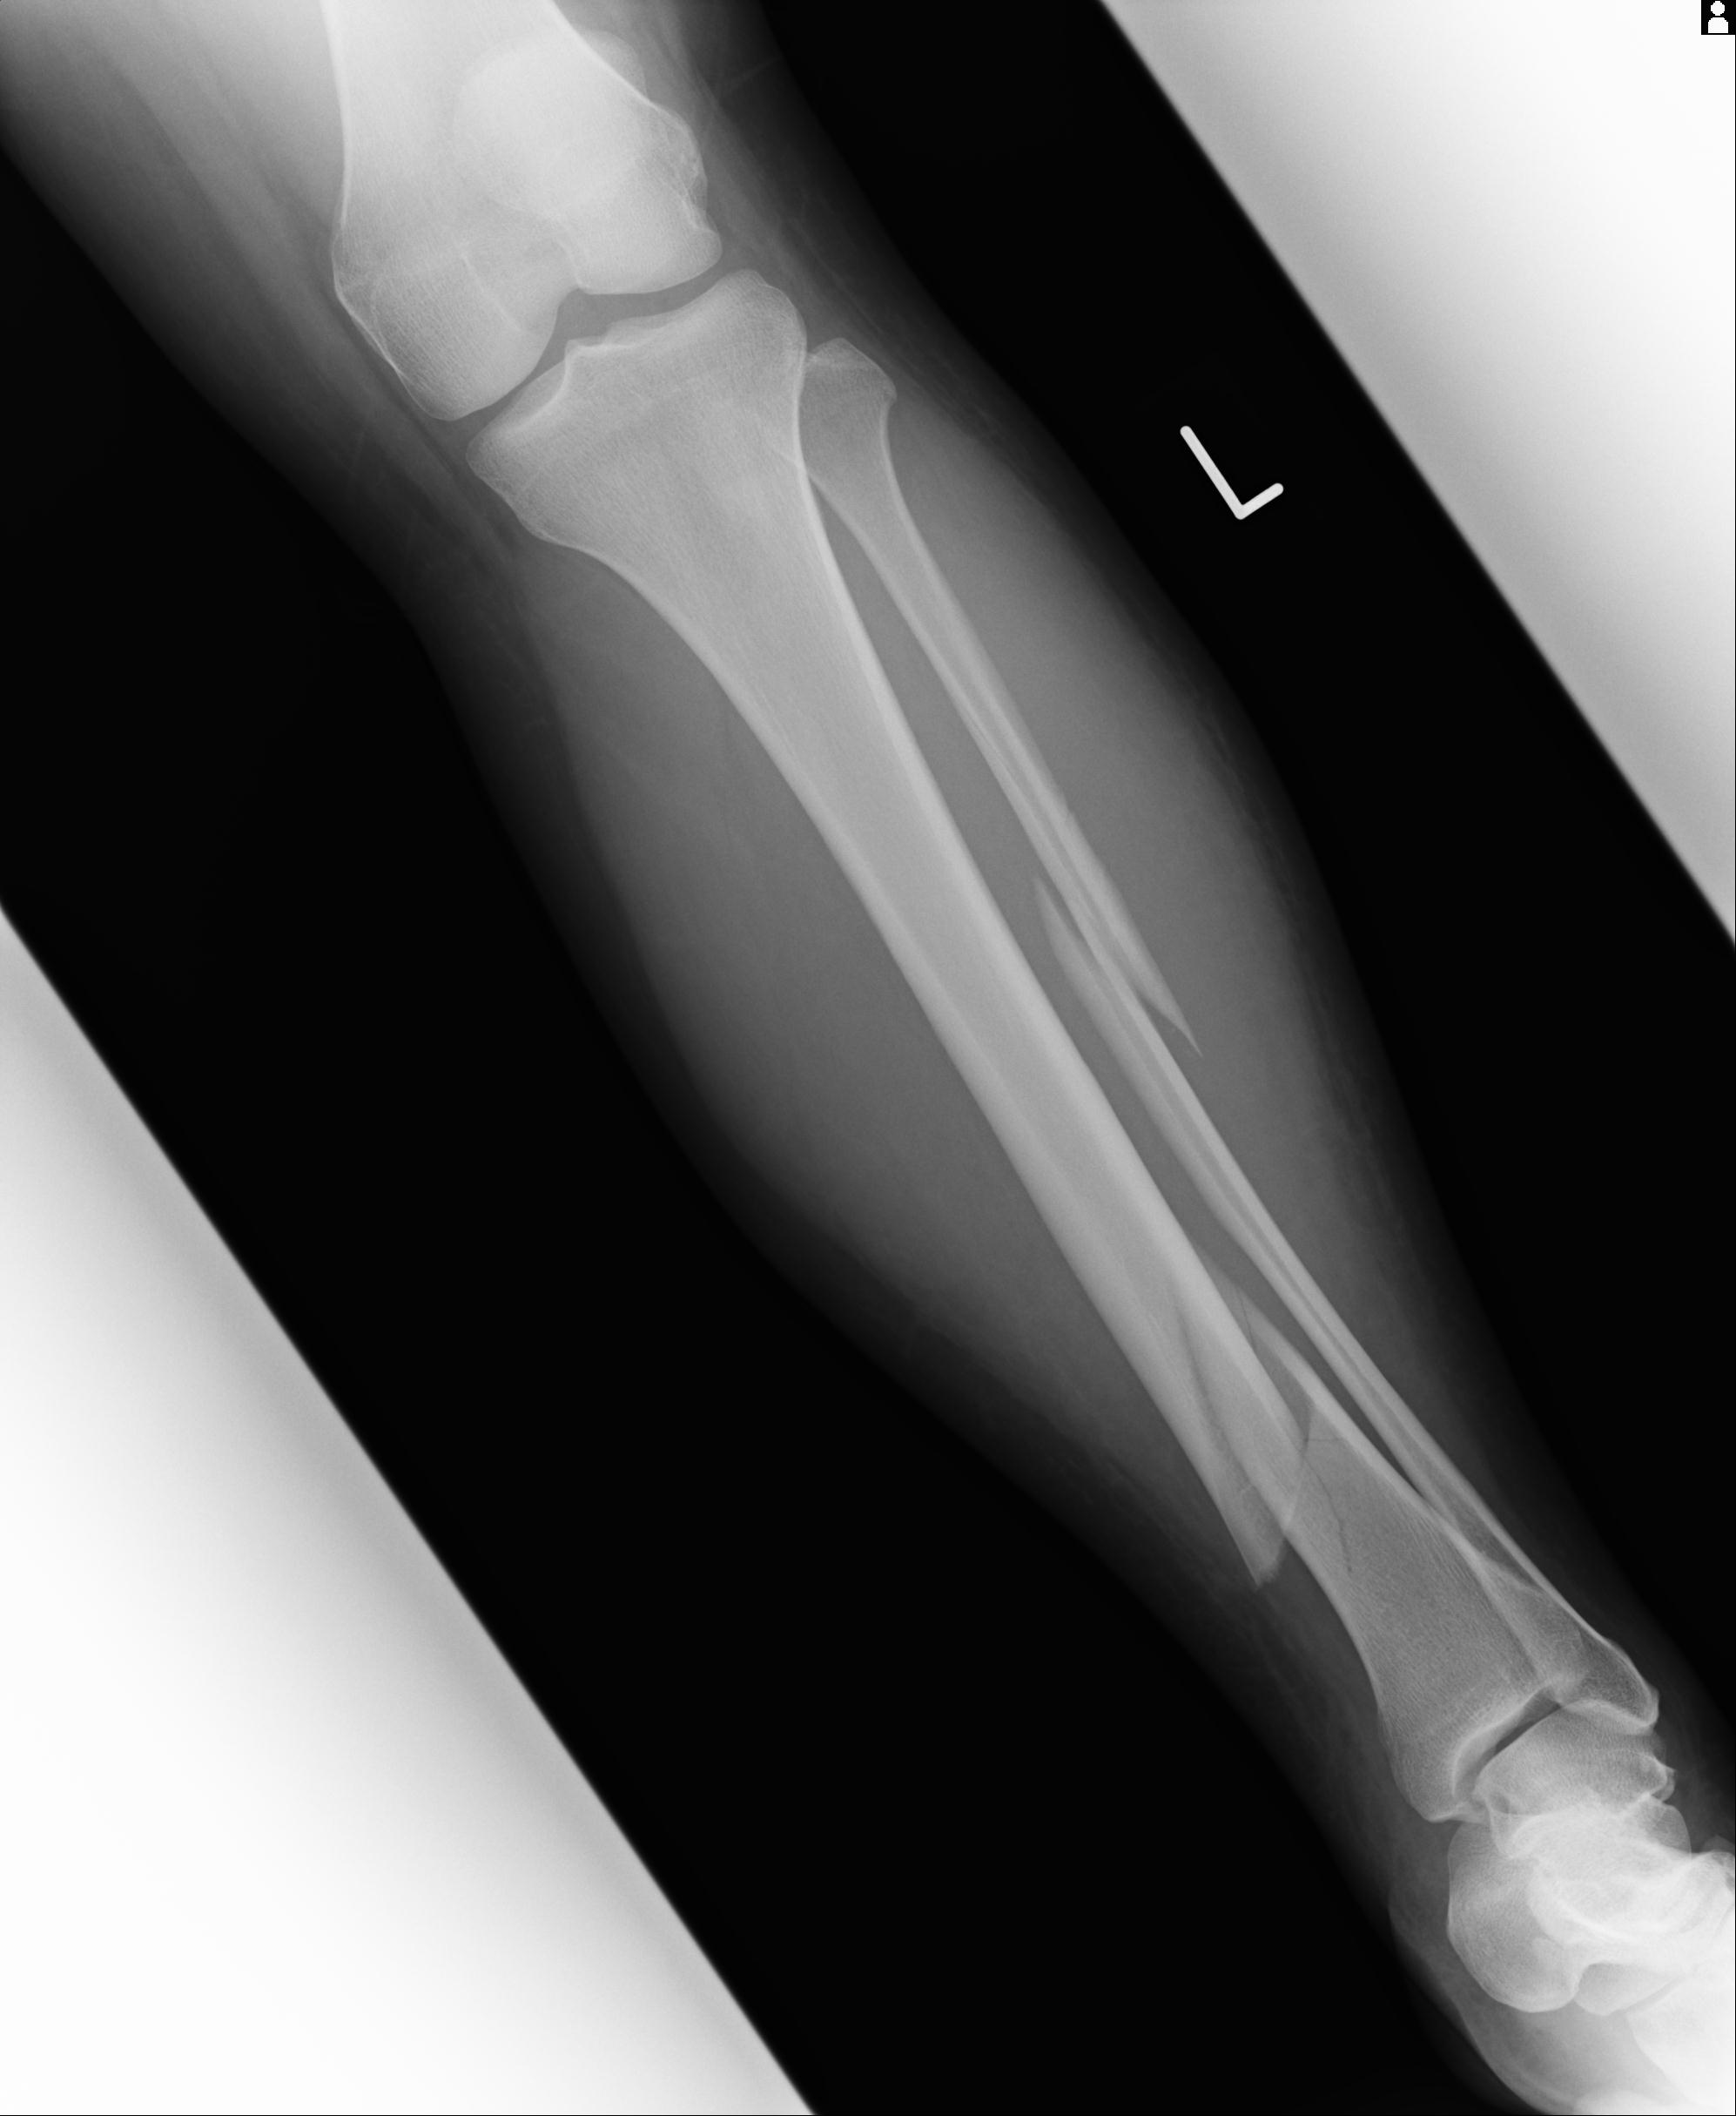

102803 1/12(キウスなし) 1/27 左下腿 4R 30歳女性 左脛骨軸内釘